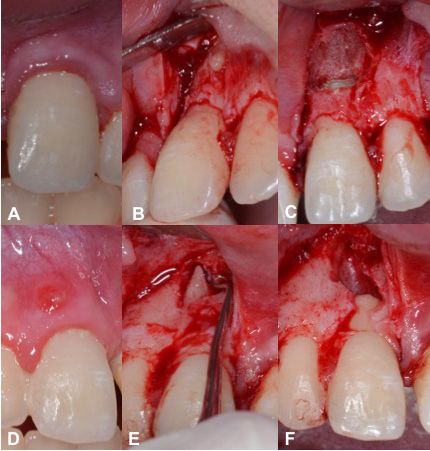

The inflammatory reaction that results in no healing is caused by the infection of the root canal system. In cases of root fracture, the infection occurs at the fracture site rather than in the periapical tissues. The coronal fragment has a “new apical foramen,” which is now situated at the fracture line rather than at the apical end of the root. Root canal therapy of the coronal fragment can be initiated and calcium hydroxide intracanal medication can be administered. If symptoms persist (i.e., abscess episodes and/or mucous fistula), an apicoectomy can be performed. Figure 4 shows the fractured apical root fragment being removed and retrograde closure of the new root apex,25 which in one case is at the apicectomy level #11 and in the other at the root fracture line #21.26, 27